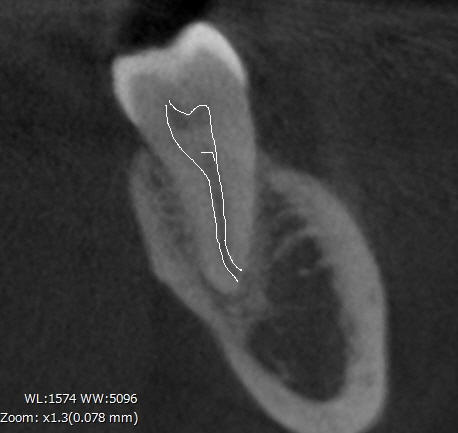

例えば同じ左下の6番目をレントゲンで撮ったものとCT撮影したものを比較すると、、、

一見すると遠心根は真っすぐのように見えますが、右のCT写真では根の先が頬側に湾曲しているのがわかります。

このような情報が事前にあるのとないのでは成功率に大きな違いがあります。